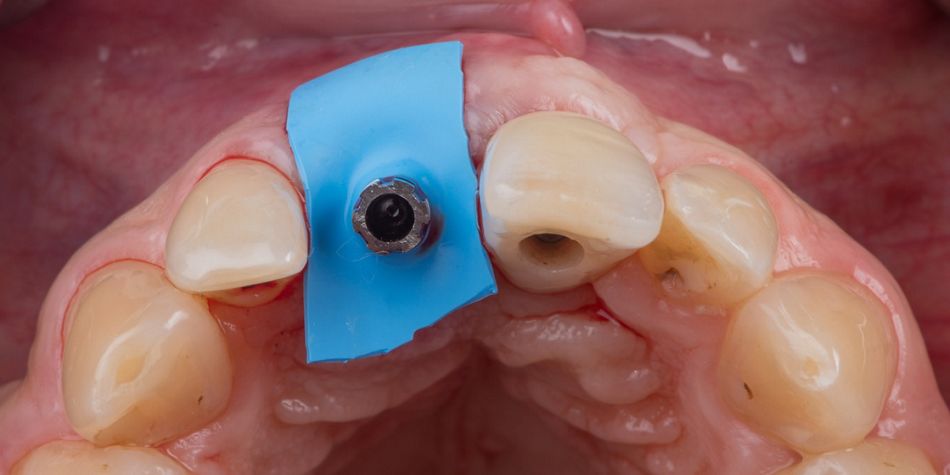

Immediate implant procedure on #11. Tooth #11 was extracted atraumatically without raising a flap or osteotomy (Fig. 4). The extraction socket was meticulously cleaned and rinsed with Betadine. The drilling sequence included 2.2mm, 2.8mm, 3.2 mm and 3.7mm drills (Fig. 5). The implant was placed with a final Torque of 80 N.cm (Fig. 6, 7). In its final position, the implant platform lied 4 mm under the ideal gingival margin (at the same level of the adjacent implant platform)(Fig. 8). A RB/WB Temporary Abutment for crown was placed and a laboratory made shell was positioned without interference of the temporary abutment (Fig. 9). The surgical site was protected with a small piece of rubber dam (Fig. 10) and the position of the abutment was connected to the shell with a dual-curing luting composite (Fig. 11). The development of a proper emergence profile will be done extra-orally (Fig. 12) to get the screw-retained temporary crown.